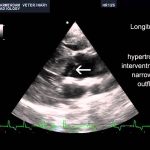

Understanding Hypertrophic Cardiomyopathy in Dogs: Symptoms, Diagnosis, and Treatment

Discover the signs, diagnosis, and treatment options for Hypertrophic Cardiomyopathy in dogs. Learn how to improve your pet’s quality of life with early detection.